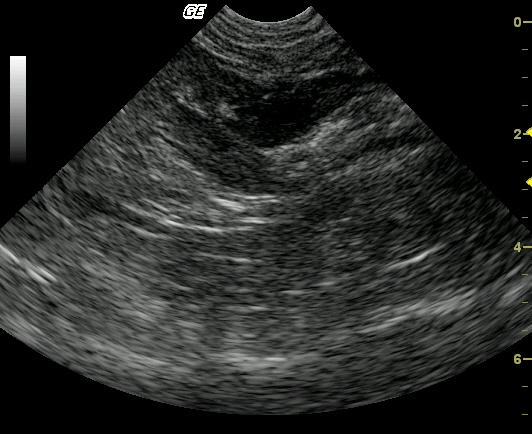

This 11-year-old FS Seal Point Siamese cat was presented for dyschezia. The physical exam revealed palpable stool impaction and a ropey intestine. The CBC and blood chemistry analysis were normal.